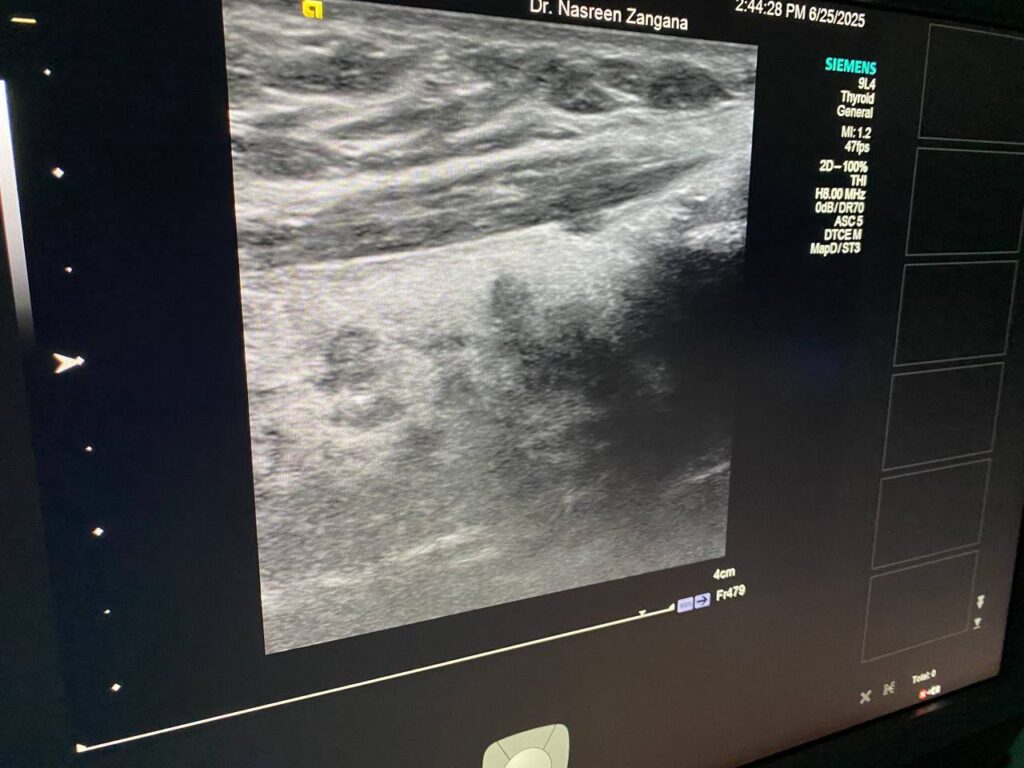

in the left sided of the isthmus presence of two hypoechoic masses , size 3.2×3.3mm, it has indistinct margin , suspicious nodule can not be exclude for further study , the other mass 3.6×2.4mm more regular , mostly lymph node , please for further study TIRADS U4